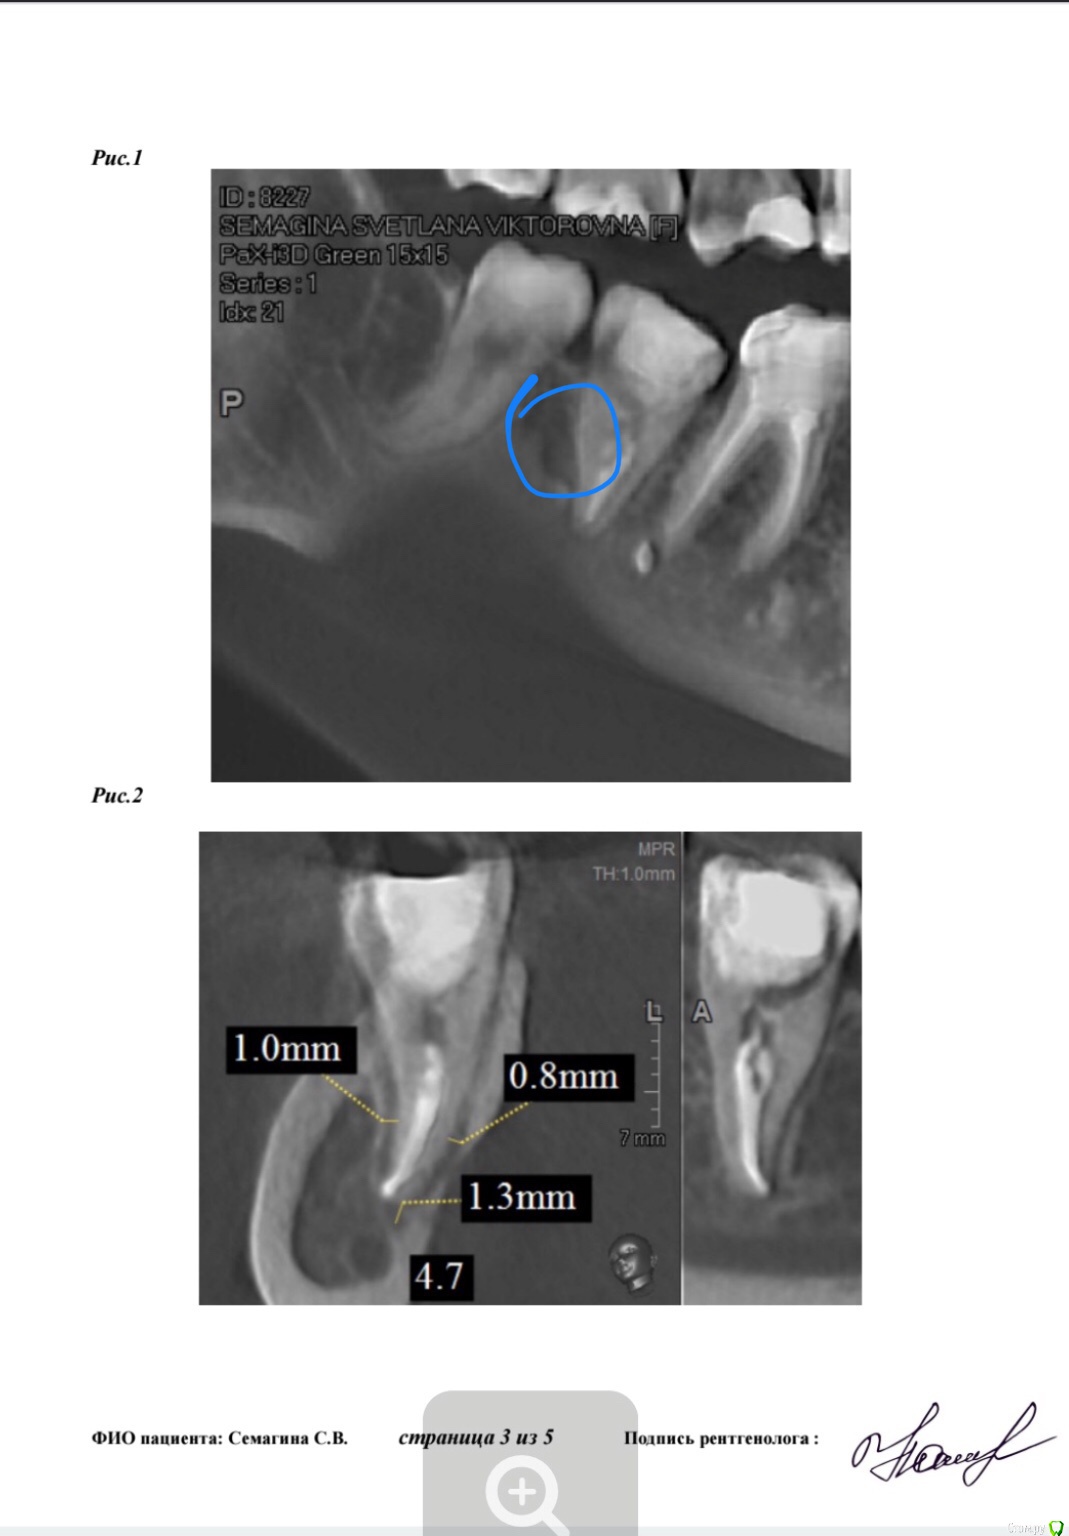

Лана-Лана Опубликовано 15 февраля, 2018 Автор Поделиться Опубликовано 15 февраля, 2018 (изменено) Сейчас зуб в таком состоянии с метапиксом( перепутала изначально сказала метопаста), вижу темное пятно слева от зуба это что воспаление? И так же вижу слева как второй корень именно корень а не канал... он как бы чуть чуть выглядывает из за первого корня , или это наслоение какое то?. в первом корне 2 канала а может быть в другом корне тоже какой то патайной канал которого воачи не видят ? Изменено 15 февраля, 2018 пользователем Лана-Лана Ссылка на комментарий

Лана-Лана Опубликовано 17 февраля, 2018 Автор Поделиться Опубликовано 17 февраля, 2018 Зуб стал болеть с метапиксом такая давящая ноющая, припухлость не уходит! Что делать дальше? Ждать ? Сказали ходить три недели! Или пойти поменять лекарство? Уважаемые доктора посмотрите последний снимок почему лекарство не до апекса? Оно вообще как то подействует на воспаление в кости в десне? Может ли быть в таком зубе третий канал скрытый? Может какой то внутри разделяется на два? По кт может что то видно? Ссылка на комментарий